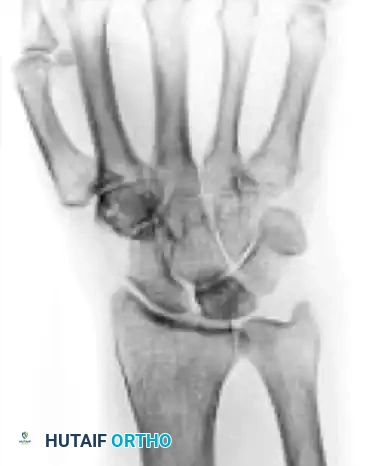

Stage IIIB

- Description: Lunate fragmentation is accompanied by fixed rotation of the scaphoid (dorsal intercalated segmental instability - DISI pattern) and proximal migration of the capitate.

- Treatment: Proximal row carpectomy (PRC) or STT fusion. The internal collapse pattern must be addressed.

4. Revascularization Procedures

For early-stage disease without collapse, vascularized bone grafting (VBG) can restore blood supply.

* Techniques: The 4+5 Extensor Compartmental Artery (ECA) pedicled graft from the distal radius, or a free vascularized medial femoral condyle graft.

* Adjuncts: Revascularization must be protected from compressive forces. This is achieved by temporary pinning of the scaphocapitate joint or application of a spanning external fixator for 8 to 12 weeks.

When the lunate has collapsed, the scaphoid has rotated (DISI), or secondary arthritis has set in, joint leveling and revascularization are no longer viable.

- Proximal Row Carpectomy (PRC): Excision of the scaphoid, lunate, and triquetrum. Converts the wrist to a simple hinge joint between the capitate and the lunate fossa of the radius. Requires a pristine capitate head.

- Scaphoid-Trapezium-Trapezoid (STT) Fusion: Halts the DISI collapse pattern and unloads the lunate by transferring forces through the scaphoid.